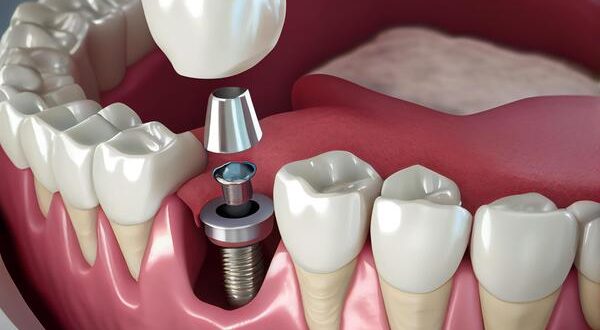

Что такое одномоментная имплантация зубов Одномоментная имплантация зубов — это метод постановки импланта и временного зубного протеза за одну процедуру или в рамках одного визита к стоматологу. В